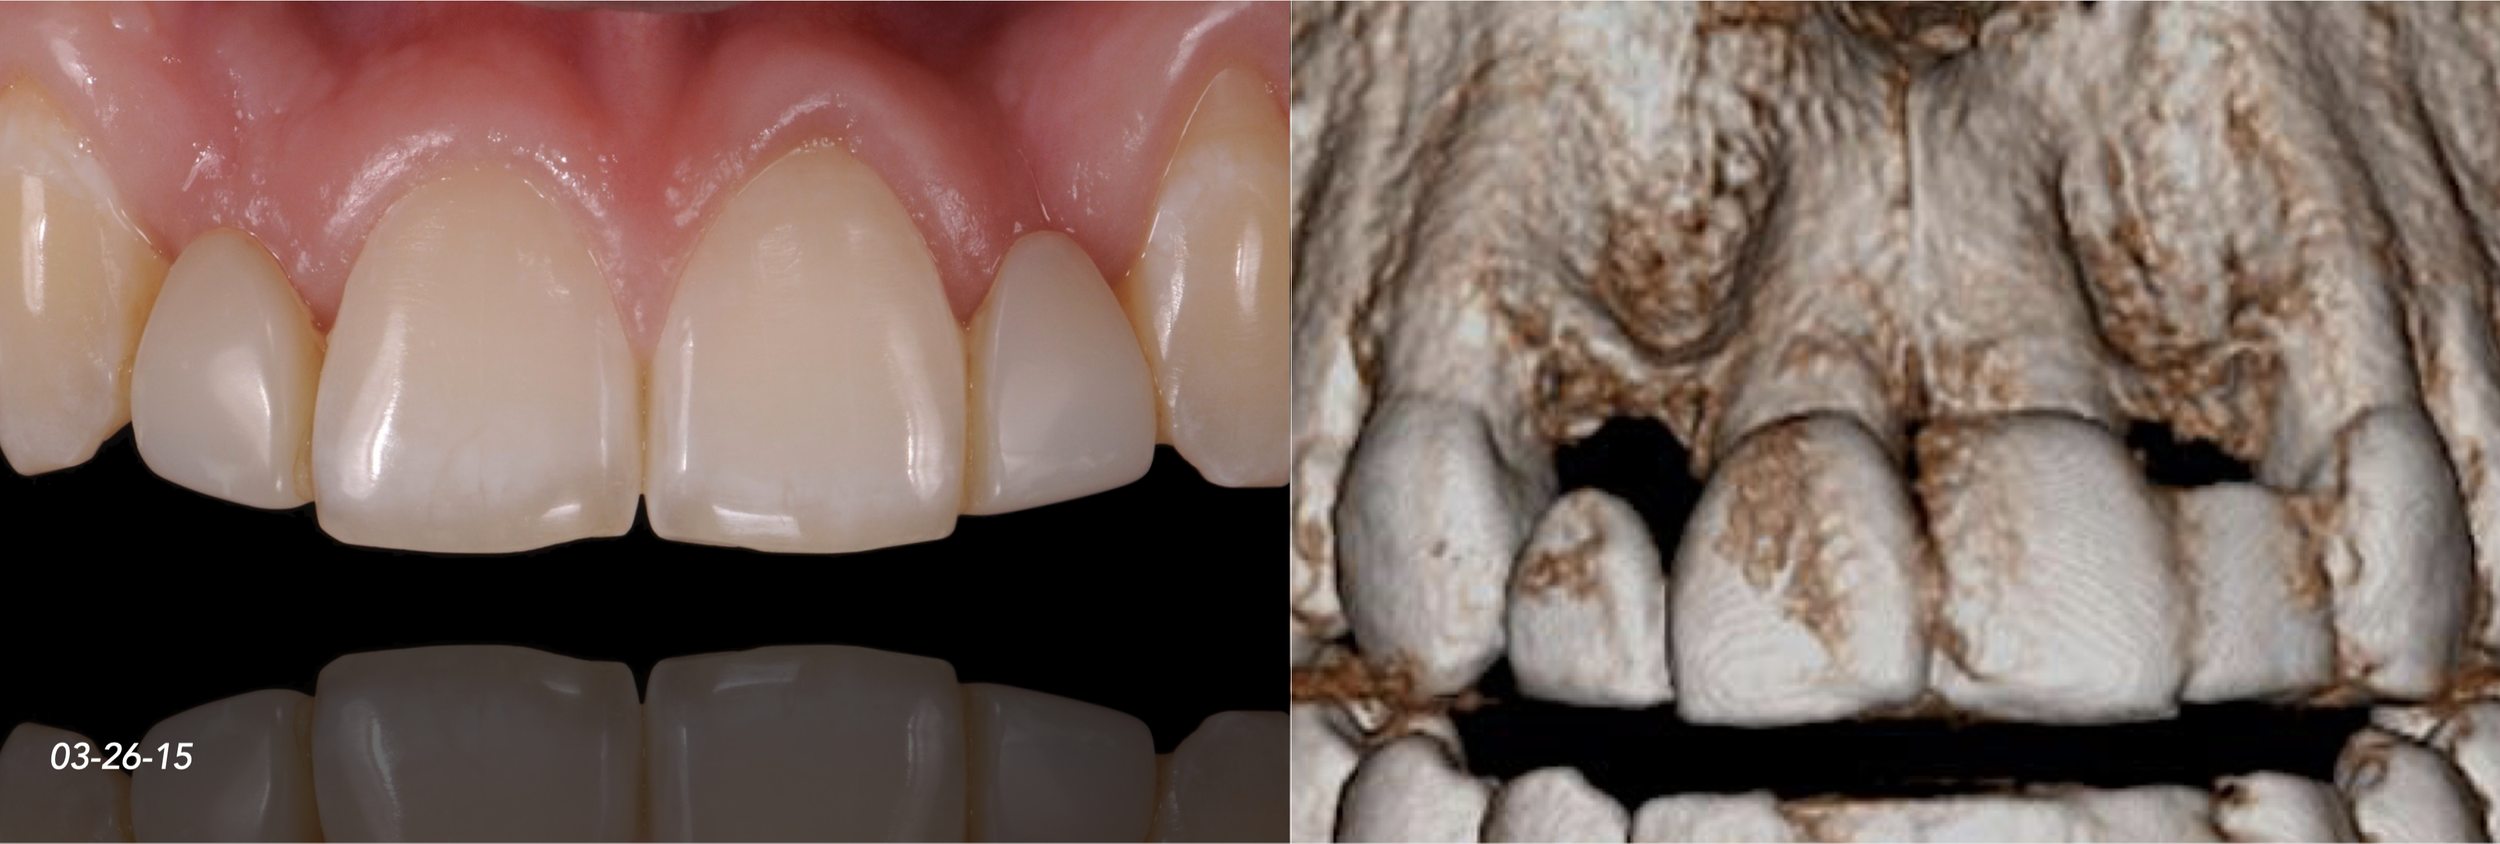

Clinical Cases CASE 1. COMPLEX IATROGENIC DEFECT CASE 2. CONGENITALLY MISSING LATERAL INCISORS CASE 3. VERTICAL AUGMENTATION CASE 4. VERTICAL AUGMENTATION CASE 5. IMPLANT BONE DEHISCENCE CASE 6. IMPLANT BONE DEHISCENCE CASE 7. KNIFE-EDGE RIDGE CASE 8. IMMEDIATE IMPLANT AND SIMULTANEOUS S.M.A.R.T.® HORIZONTAL AUGMENTATION CASE 9. IMMEDIATE IMPLANT AND SIMULTANEOUS S.M.A.R.T.® HORIZONTAL AUGMENTATION